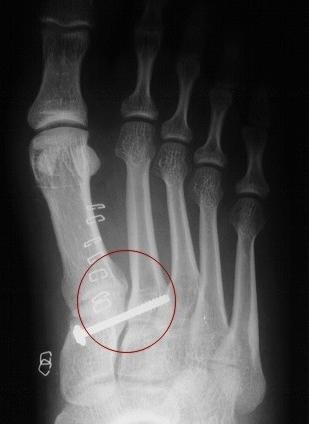

Figure 4: Post operative x-ray. Notice how the distance between the 1st and 2nd metatarsals and the cuneiform bones is now normal. Compare to figure 1 and figure 3. The red circle represents the area of the fixed Lisfranc joint between the 1st and 2nd metatarsals and the medial cuneiform bone.

Once instability at the midfoot joints has been established. The treatment is usually surgical if a significant separation of the bones exists. Surgical treatment usually requires that pins and/or screws be inserted to stabilize the bones and joints. This procedure is called an open reduction and internal fixation. This allows the normal anatomy to be re-established.